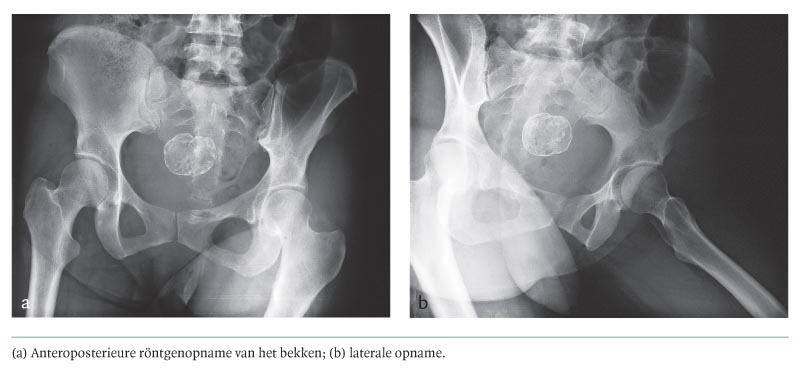

Diagnose in beeld (336). Een vrouw met een verkalkte pelviene massa

Een 34-jarige vrouw kwam tijdens haar vakantie in Frankrijk ten val en meldde zich op de afdeling Spoedeisende Hulp van een Frans ziekenhuis met pijn ter hoogte van haar bekken. Ter uitsluiting van een fractuur werd een röntgenfoto van haar bekken genomen. Er waren geen aanwijzingen voor fracturen, maar wel was er een opvallende, schaalvormige, verkalkte massa met een afmeting van 3 bij 3,5 cm te zien in het kleine bekken (figuur). De radioloog stelde de diagnose ‘gecalcificeerd uterusmyoom’ en patiënte werd met pijnstilling uit het ziekenhuis ontslagen. Zij was een gezonde para 2 en was reeds…